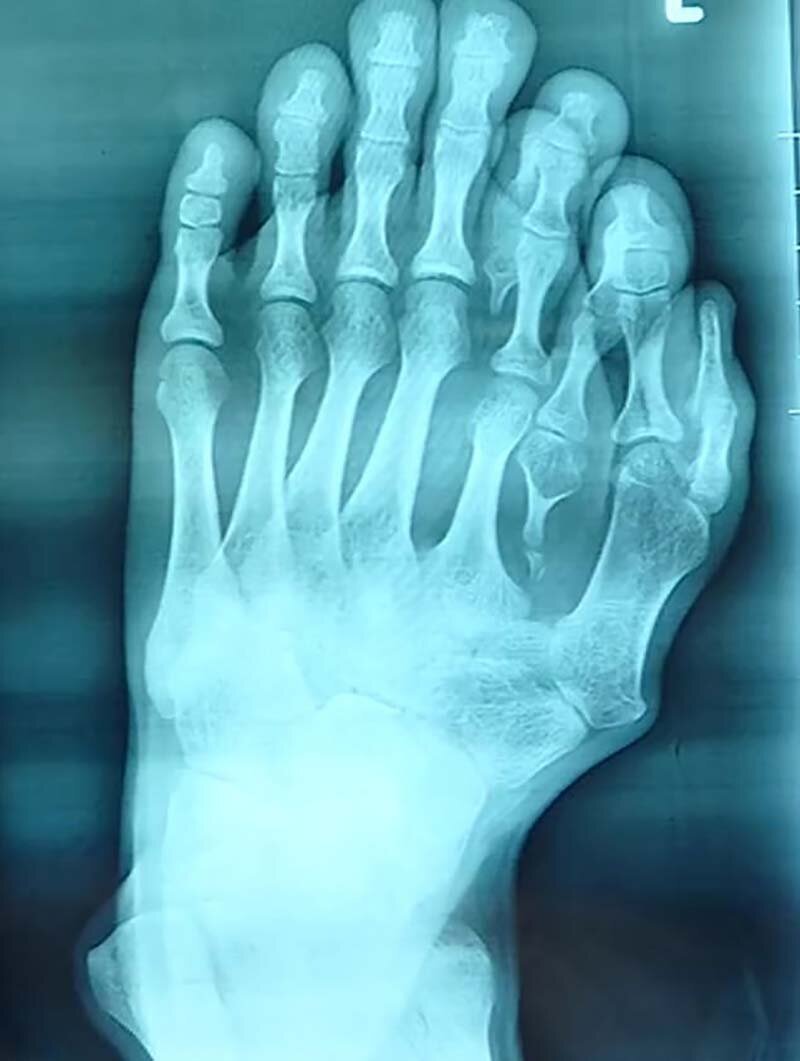

Сделанные предоперационные фотографии и рентгенограмма показали врачам степень тяжести деформации

Пальцы поменьше выросли между пальцами его нормального размера. При этом у парня не хватало большого пальца, вместо него у него сформировались два маленьких пальца, образовавших букву «V».

«Очень редко можно повстречать столь ??серьёзную деформацию у 21-летнего пациента, которую не лечили», — сказал доктор Ву Сян (Wu Xiang) из больницы города Фошань.